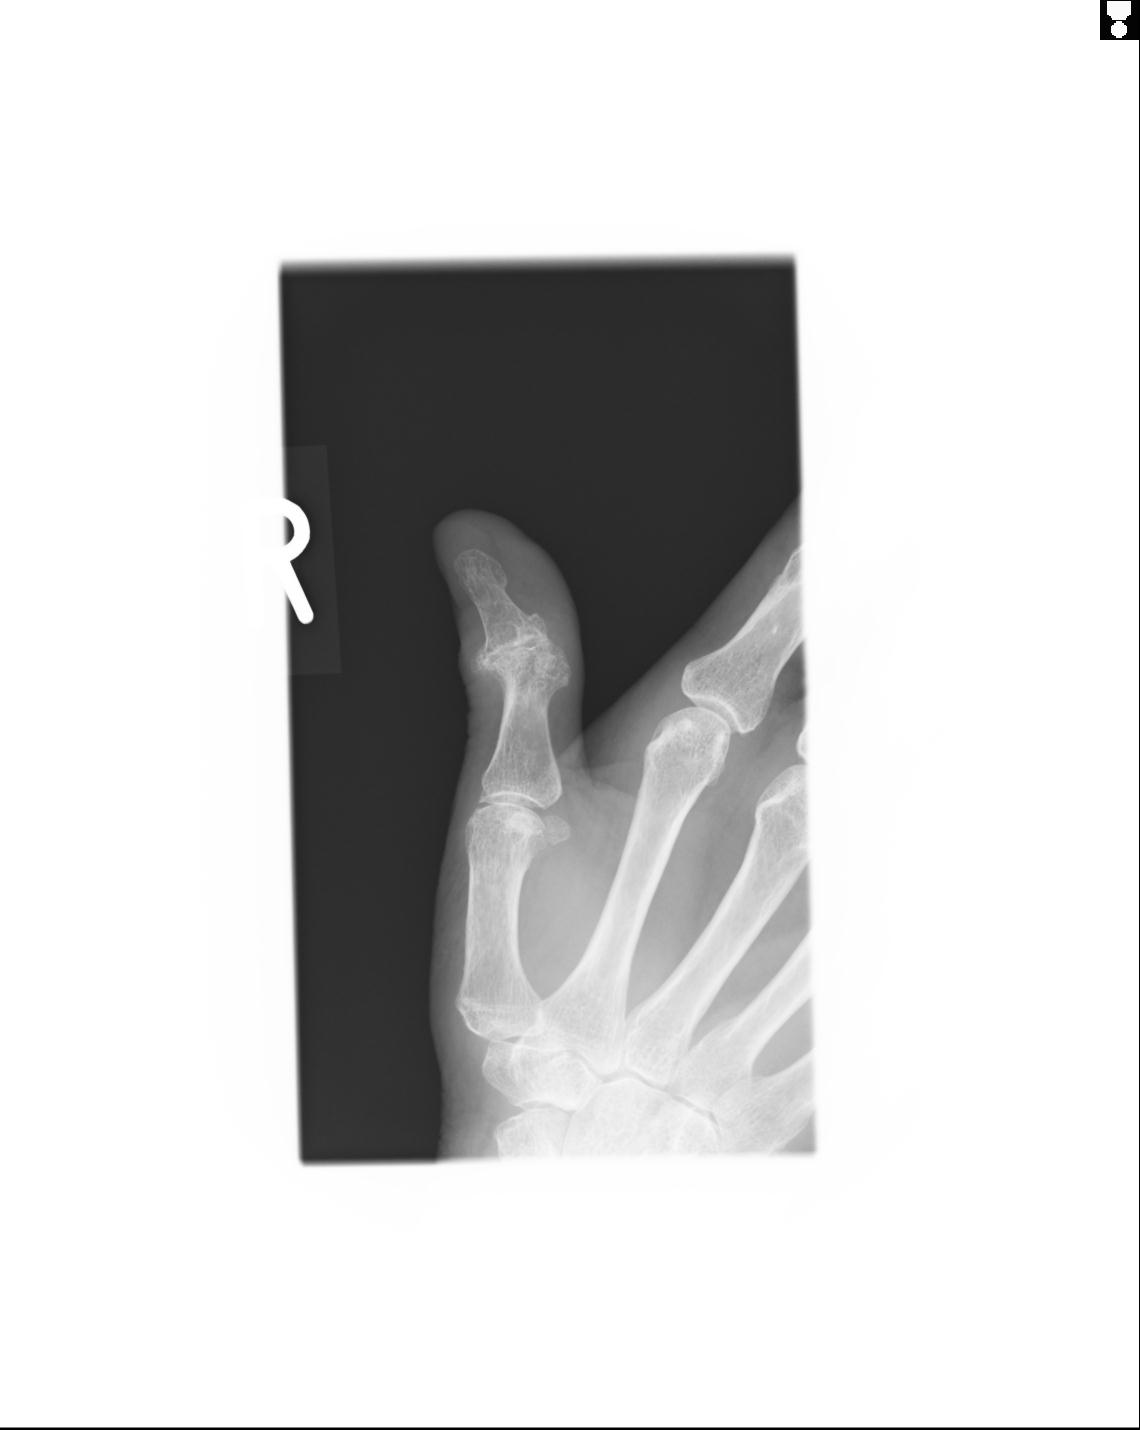

102860 1/21 (4R) 1/26 (4R) 3/15 左手 2R 91歳女性 左環指中節骨

20857 1/11 左手 3R 1/19 4R 55歳男性 小指中節骨骨折